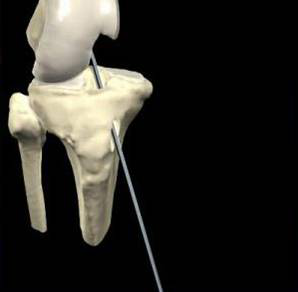

脛骨點選取

股骨點